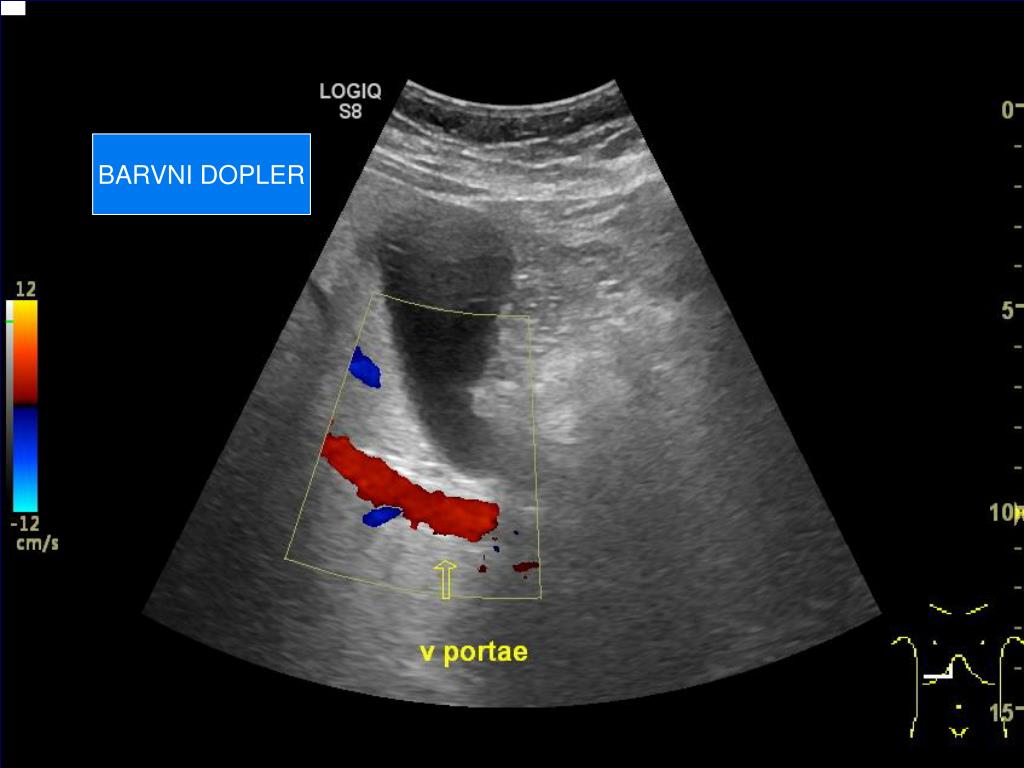

17. BARVNI DOPLER